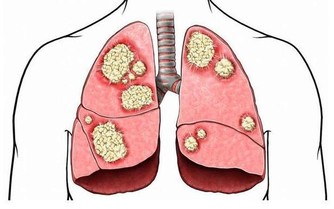

關節的壽命是有限的。一旦關節“氣數已盡”,就會引發各種關節病!關節的壽命主要是由基因決定的,一般的健康壽命是60年。

一方面,大家需要鍛煉大腿和臀部的肌肉群。但是另一方面,大家又不能以傷害膝關節為代價。過度使用會加重對它的磨損,並且不可修復。